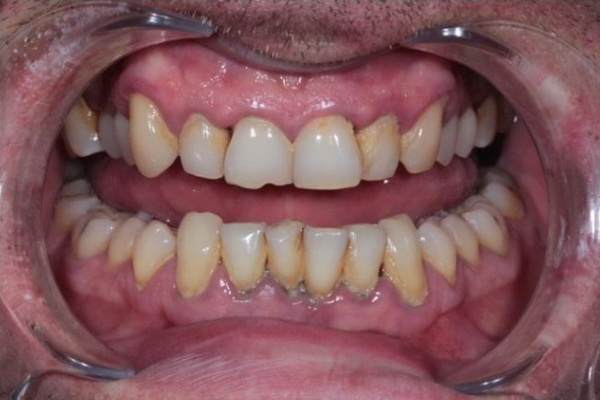

Стан ясен та зубів через 4 місяці після лікування (до та після проведення планової професійної гігієни ротової порожнини).